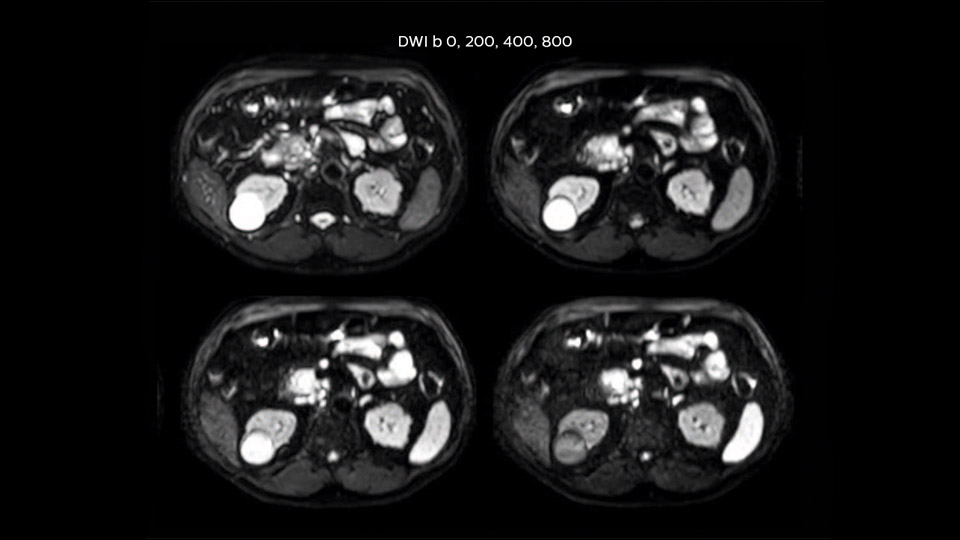

In this example the image quality of the MultiVane XD images is evidently better than in the images without MultiVane XD. Ingenia 1.5T with dS Torso coil solution.

“Our liver exams are quite fast,” says Dr. Baumann. “If the patient tolerates it, we use an arms-up position to reduce the FOV and speed up the exam with dS SENSE.” “We acquire one transversal high resolution T2-weighted sequence with 3 mm slice thickness, for example for pancreas or liver lesions. Then we also add a T2 fat suppressed MultiVane XD SPIR sequence. We perform these two routinely in our liver imaging. We use high dS SENSE factors to significantly shorten scan times to 2-4 minutes, which can improve our protocol; it’s a very robust scan.” “We include mDIXON for the dynamic sequences because of the robust and homogeneous fat suppression we get with that. We had been using eTHRIVE, but we are now quite happy with mDIXON. Sometimes we use a medication to calm the bowels, to further improve the image quality.”